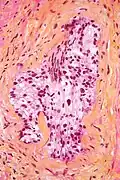

- Invasion périneurale par un adénocarcinome prostatique. HE, x200

Invasion périneurale par un adénocarcinome prostatique. HE, x200